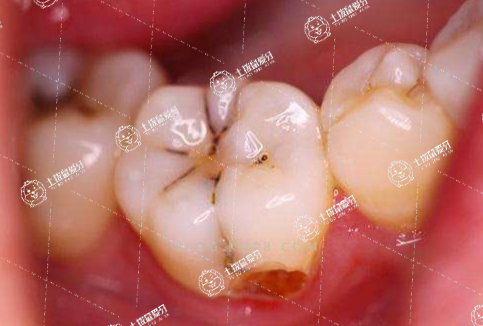

補(bǔ)一顆牙齒大約需要半小時到兩周左右。牙面上形成小面積齲洞時,可直接磨除變色牙體組織、制備洞型后,應(yīng)用復(fù)合樹脂等充填,約需30~40分鐘。如果齲壞面積較大,有時破壞鄰接點,除了要去除腐質(zhì)和薄壁弱尖外,還要制備鳩尾固位形等,應(yīng)用玻璃離子水門汀等修補(bǔ),恢復(fù)鄰接關(guān)系,約需50~60分鐘。如果牙髓暴露在齲洞內(nèi),形成牙髓炎或根尖周炎時,需在局麻下摘除牙髓,根管預(yù)備、消毒后封閉管腔,修補(bǔ)窩洞,整個過程約需兩周左右。

不雅的具體時間要根據(jù)實際的情況決定,如果牙齒剛剛齲壞,沒有傷到牙神經(jīng),補(bǔ)牙一只就可以完成,補(bǔ)一顆牙齒應(yīng)當(dāng)在半小時左右。如果牙齒疼痛就需要做根管治療,根管治療大概要3至4次,時間應(yīng)當(dāng)在三到四周的時間,每次在30分鐘左右如果只是簡單的補(bǔ)牙的話,當(dāng)時去,當(dāng)時就能不上,比較嚴(yán)重的,需要去除被蛀的部分,然后再消炎,補(bǔ)牙。更嚴(yán)重的那就需要做根管治療,然后再補(bǔ)牙,時間大概在一個星期左右。